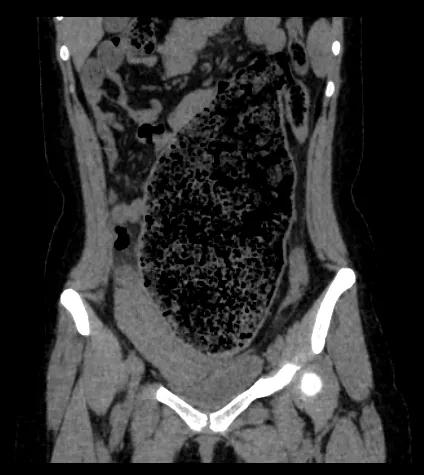

△小静的整个腹腔充满了便便